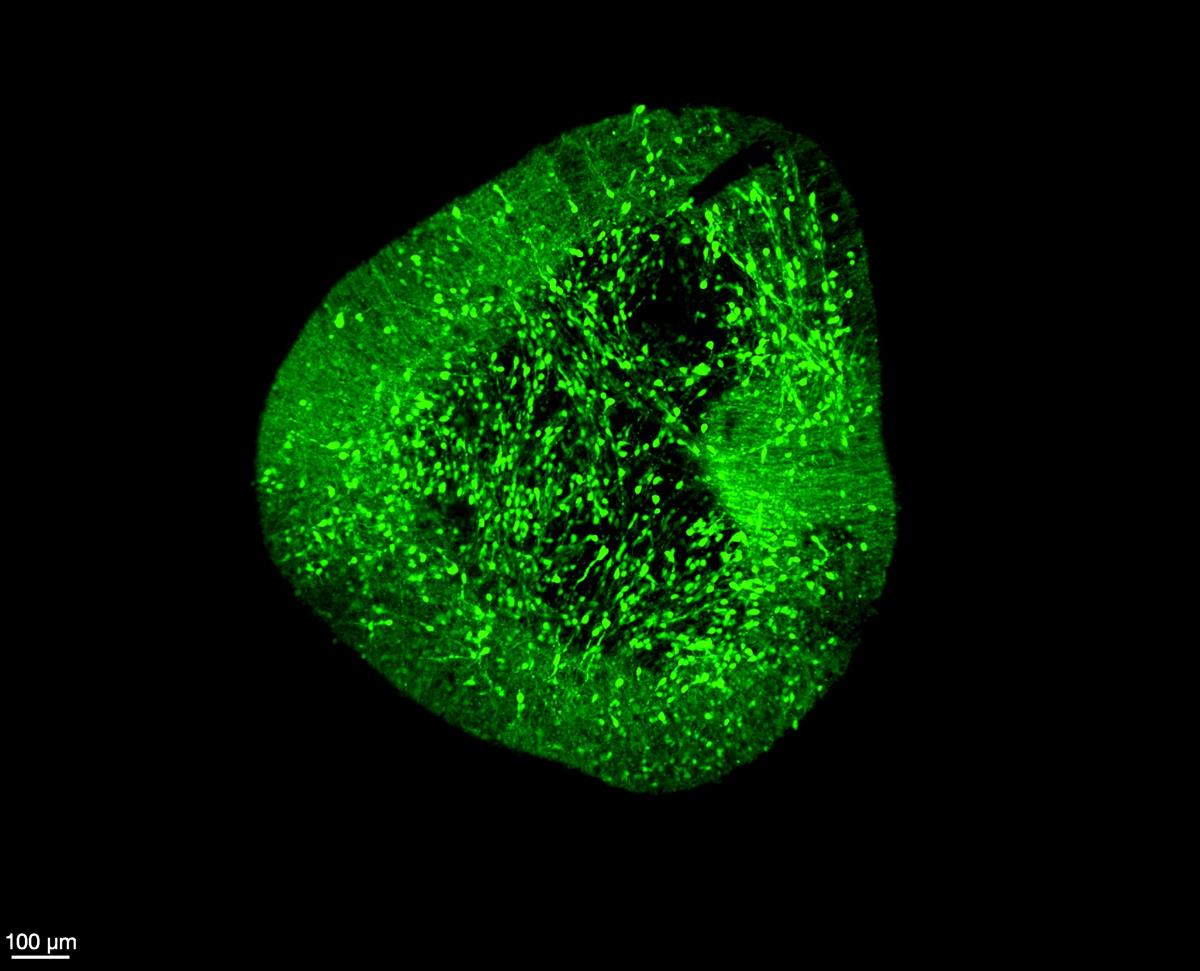

Midbrain dopaminergic neurons under a microscope (Image credit - Hilary Toh, Duke-NUS Medical School)

Midbrain dopaminergic neurons under a microscope // Image credit: Hilary Toh, Duke-NUS Medical School